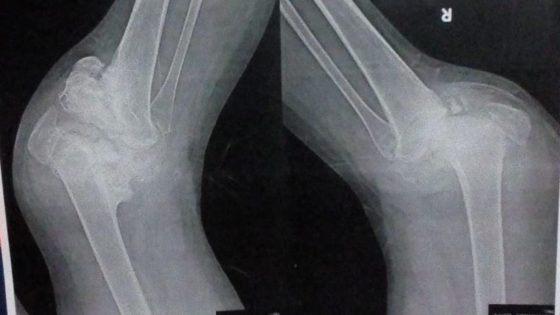

الفتاة تعايشت مع السكري من النوع الأول منذ كانت في الصف الأول الابتدائي، ولم تكن تعلم أن القدر يخبئ لها اختبارًا أصعب، وهو إصابتها بمرض “شاركوت” (اضطراب عصبي نادر) أدى إلى تلف أعصابها، وتفتت كامل لعظام مفصلي ركبتيها وتآكلهما.

أتضح للأطباء أن الركبة تآكلت بنسبة كبيرة، وتحتاج إلى توافر إمكانيات تقنية حديثة لتركيب ركبة تعويضية بمواصفات دقيقة لا توجد في مصر، بالإضافة إلى ارتفاع نسبة المخاطر في حال إجراء الجراحة محليًا، ما قد يؤدي إلى العجز الكامل أو البتر.